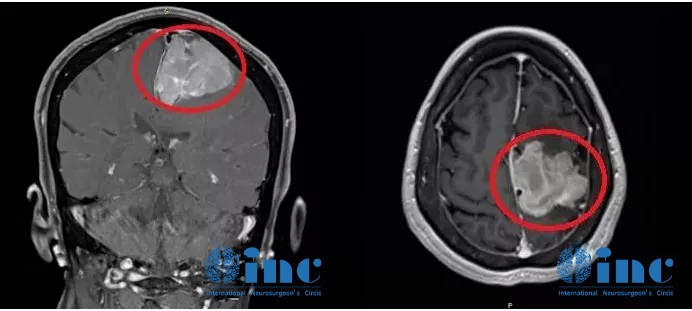

今年60多歲的退休老師王女士在2012年就檢查出有“左側(cè)額部大腦鐮旁腦膜瘤”,由于腫瘤不到3cm加上無癥狀,前沿行了保守治療。2018年復查,腦膜瘤已大于5cm,逐漸出現(xiàn)肢體無力,復查MR顯示腫瘤侵犯靜脈竇、壓迫功能區(qū)。

國內(nèi)各大醫(yī)院求診,均被告知手術(shù)難度大,腫瘤因為靠近大靜脈竇難以全切,且腫瘤靠近運動功能區(qū),術(shù)后癱瘓可能較大(60-全切不等),而這對于人和一個人和家庭都是慘痛的,除了生活難以自理的經(jīng)濟負擔,對于病人和家人也是巨大心理負擔。

家人輾轉(zhuǎn)求醫(yī)找到INC德國巴特朗菲教授,王女士的治療才迎來轉(zhuǎn)機。在教授所在的德國INI國際神經(jīng)學研究所、由INC德國巴特朗菲教授主刀的一場高質(zhì)量手術(shù)直接全部切除了患者大腦深部復雜部位的腦膜瘤,她大腦中的“定時炸彈”被完全摘除。如今手術(shù)已過去了1年半,從其術(shù)前MR、剛手術(shù)后的MR、術(shù)后1年半多的MR可以清楚看到未見復發(fā)跡象,患者現(xiàn)在生活如常,幸福的晚年生活不必再被可怕的腫瘤打擾。

術(shù)前MR

腦膜瘤術(shù)前

術(shù)后MR

腦膜瘤術(shù)后

術(shù)后一年半MR

腦膜瘤術(shù)后一年半